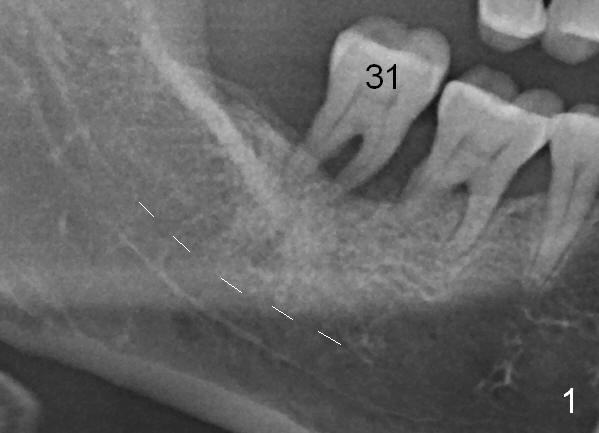

A 46-year-old lady has generalized moderate localized severe (Fig.1 (panorex) #31) chronic periodontitis. Surprisingly there is sufficient bone height (Fig.1 white dashed line: upper border of the Inferior Alveolar Canal). The gingiva is quite thick (Fig.2 (PA) arrowheads: gingival margin). In order to prevent thread exposure associated with immediate implant, a bone-level implant will be placed (Fig.3 5.3x8 mm; green lines) with a long abutment (5.8x5.5 mm (black lines) (6 mm cuff; red lines)). Initial osteotomy depth is between 14 and 17 mm. Insert a parallel pin and take the 1st intraop PA. Use reamers to enlarge osteotomy and collect autogenous bone. A drill with a stopper (5x8mm) will be used prior to placement of the implant mentioned above. Since the opposing is a removable partial denture, an immediate provisional at the site of #31 should be safe to be fabricated. Bone graft will be placed to cover the exposed implant surface. The remaining gap will be filled with collagen dressing and the provisional. A temporary abutment is the other option. The shoulder of the temporary abutment will be subgingival to long extent. Is the plan well executed?